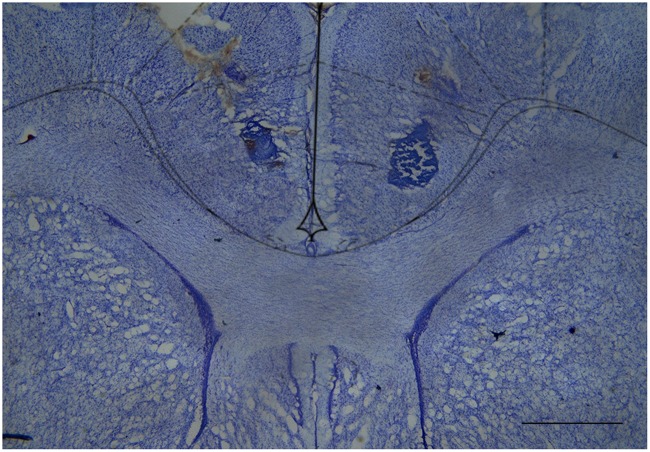

Histology

After the tests, the rats were deeply anaesthetized with a lethal dose of chloral hydrate (500 mg/kg intraperitoneally) and transcardially perfused with 0.9% saline followed by 10% formalin. The brains were removed and post-fixed in 10% formalin followed by a 10% formalin/30% sucrose solution until sectioning. Coronal brain sections (60 μm) were cut on a cryostat and wet mounted on glass microscope slides. Once dry, the sections were stained with cresyl violet (5%, Sigma–Aldrich) to visualize and identify microinjection sites by microscopic examination, according to the atlas of ref. Paxinos and Watson (2006).

CBD Injection into the rACC Reduces Mechanical Allodynia in Incised Rats

The great majority of injection sites were concentrated in the rACC (2.28 to 1.80 mm in relation to bregma). Representative photomicrograph of injection sites is shown in Figure 4. Time line of the protocol for the experiments is shown in Figure 5A. The local injection of CBD (40 nmol/0.25 μL) produced a reduction of the mechanical allodynia that lasted for at least 120 min. The decrease of mechanical allodynia started 20 min after CBD (10 and 40 nmol/0.25 μL) but was maximal at 90 min after the highest dose, which elicited a significant increase in the force required for paw withdrawal. The differences were statistically significant in terms of time [F(7.476) = 133.4; p < 0.01], treatment [F(5,68) = 134.1; p < 0.01] and interaction time × treatment [F(35,476) = 17.2; p < 0.01]. The threshold of the non-incised hind paw did not change throughout the period of observation (Figure 5B). Figure 5C illustrates the microinjection sites in the rACC on diagrams of cross-sections from the atlas of ref. Paxinos and Watson (2006).